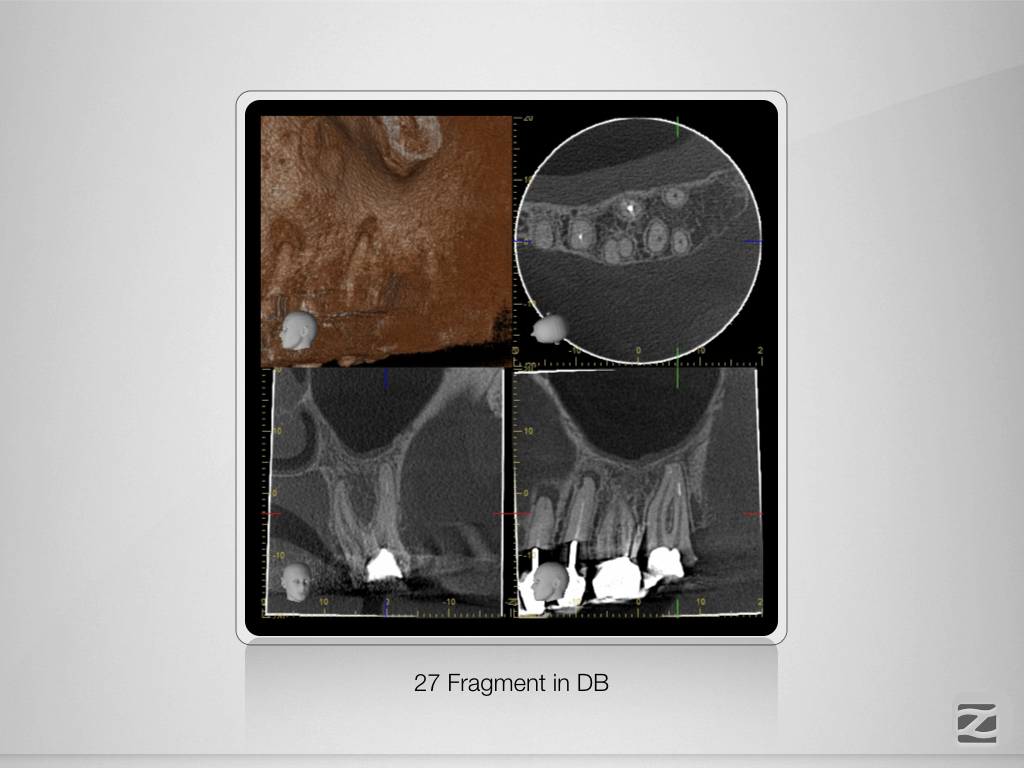

27D.002

Praxistauglicher Kompromiss